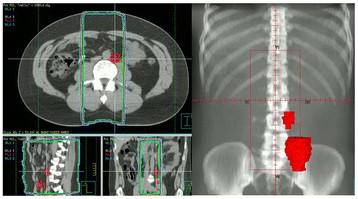

METHODS

Seventy four patients with pure seminoma were treated at King Hussein Cancer Center (Amman, Jordan) between 2003 and 2010. All patients underwent orchiectomy. All but 3 patients received adjuvant radiotherapy. Patients who underwent surgical violation of the scrotum prior to referral were managed by further excision or irradiation of the scrotal scar. The follow-up ranged from 1 to 200 months (mean, 33 months).